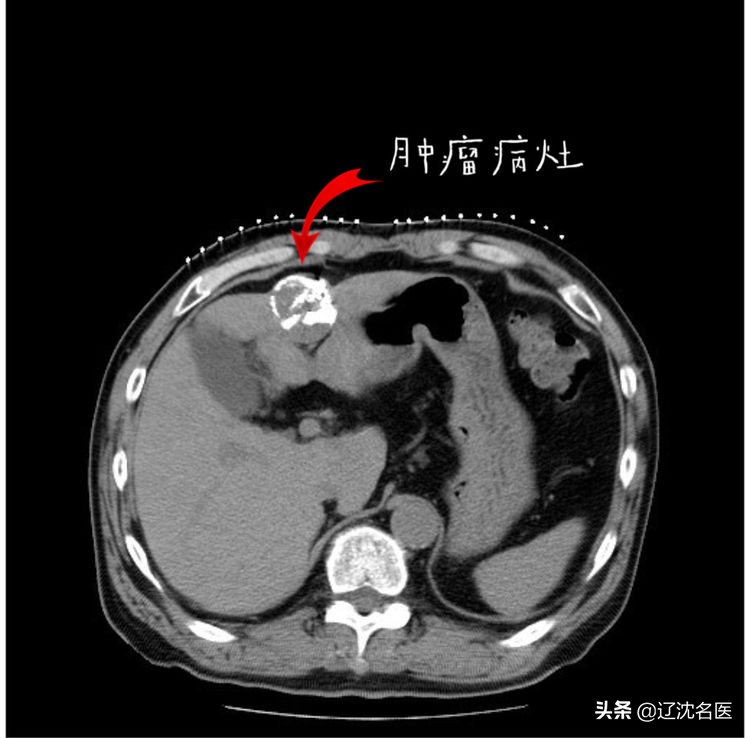

患者术前CT

2019年4月,患者就诊于外院,经CT检查,考虑肝细胞癌合并门脉左支癌栓形成、腹腔淋巴结转移。

2019年04月23日,患者行肝脏肿物穿刺活检提示“肝细胞癌”。